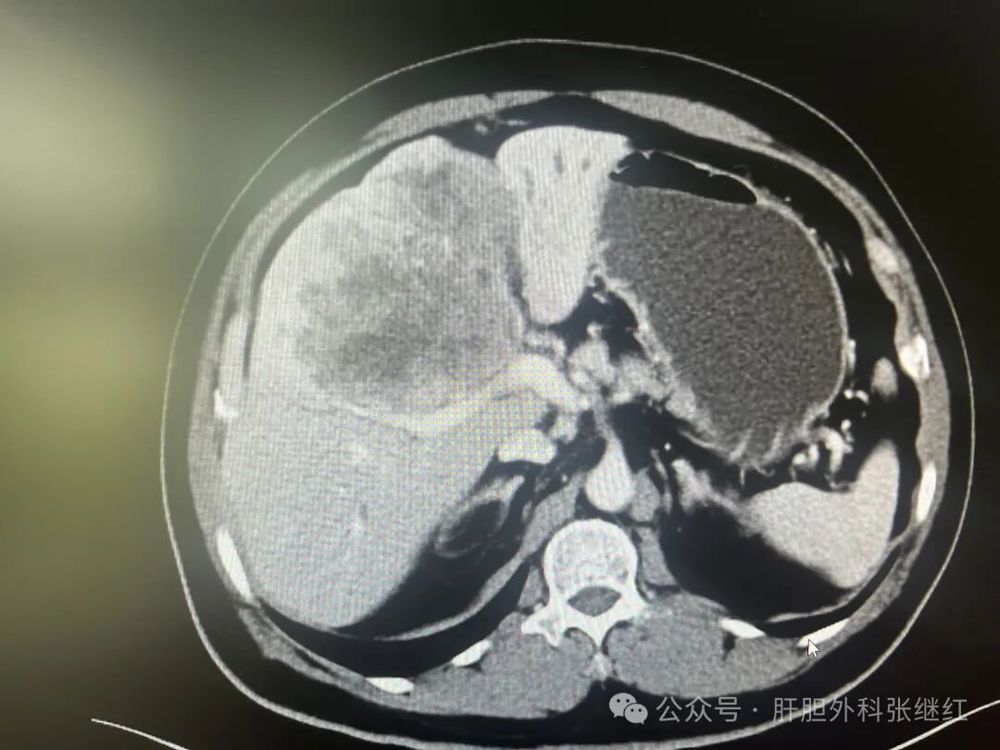

该患者是佛山复星禅诚医院肝胆胰外科病例,张继红医生有幸参加了术前多学科会诊和手术。1年前,一男性56岁病人,经CT、MR等影像学检查和病理活检确诊为胆管细胞癌,瘤体巨大,长径超过10厘米,且伴门静脉左支癌栓形成和多发腹腔淋巴结转移,经多学科会诊后决定应用吉西他滨和奥沙利铂化疗联合PD-L1单抗(度伐利尤单抗)免疫治疗进行转化治疗后再手术切除。经上述化疗联合免疫治疗五个疗程(每次均为单次给药,间隔时间21天)治疗后肿瘤明显缩小,直径约5厘米,淋巴结病灶也有所减少或缩小,达到了影像学部分缓解和手术切除的标准,经多学科会诊后决定行扩大左半肝切除及区域淋巴结清扫术,术后再行辅助治疗。本为腹腔镜手术,术中见左肝肿瘤萎缩明显,肿瘤压迫右侧肝蒂,肝门部及肝总动脉周围未见明显肿大淋巴结,肝门部粘连严重,仅清扫12a、12b、7-9组淋巴结所在区域脂肪淋巴组织,解剖离断左肝动脉、门静脉左支及左肝管,发现肿瘤基本位于缺血范围内,超声引导下在缺血线和S5段肿瘤外侧画切肝线,拟切除包括胆囊的S5段和左半肝,15+5min模式间歇性阻断肝门,沿预切线离断肝实质,达右肝蒂时发现肿瘤紧贴右肝蒂,为避免右肝蒂损伤,中转开腹完成整块切除包括胆囊的S5段及左半肝。手术后病理证实肿瘤100%坏死,清扫淋巴结亦未发现肿瘤细胞,达到病理学完全缓解(pCR)。术后早期肝断面少许积液,经引流后积液消失。目前病人状态良好,已无瘤生存半年余。

3a80572f59554b08b595c7e926806cf3.jpg  手术后病理

此例胆管细胞癌转化治疗后达到影像学部分缓解(PR)的标准,而病理证实达到了病理学完全缓解(pCR),说明该例胆管细胞癌转化治疗获得巨大成功。结合文献报道和最新指南,可以得出结论:化疗联合PD-L1单抗免疫治疗对部分中晚期胆管细胞癌患者确能转化成功并手术切除,颠覆了很多医生和病人的传统认知。化疗联合免疫治疗加手术切除治疗胆管细胞癌是划时代的进步。随着免疫研究的突破性进展和新型免疫药物的问世,以手术治疗为主的胆管细胞癌治疗还将取得更大突破。